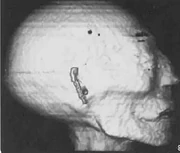

CT image of the mummy's head

In 1988, using a portable CT scanner, research altered many of the conclusions from the earlier exam: the mummy was most likely 30 to 40 years old when she died, and she stood only 5 feet 2 inches tall.